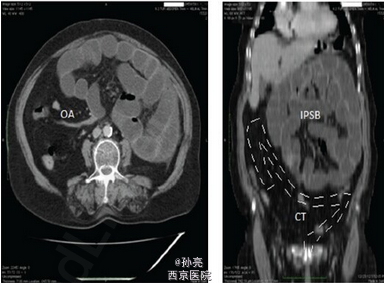

患者表现为腹痛腹胀、肛门停止排气排便、恶心呕吐 2 天。既往有高血压病史 10 年,慢性阻塞性肺部疾患 6 年,2 型糖尿病 4 年。无腹部手术史,无创伤、黄疸、直肠出血、体重减轻。体格检查表现为腹部膨隆、肠鸣音亢进、全腹压痛、腹肌软、无反跳痛。直肠指检发现壶腹部空虚。实验室检查为白细胞 12,500K/L,血糖 150mg/dL。影像学检查提示左侧小肠肠腔扩张,远端回肠和结肠塌陷(下图 1)。于是进行探查手术。术中发现扩张的空肠和回肠袢被腹膜囊包绕,位于胃和横结肠之间。末端回肠嵌顿进横结肠系膜正下方,且大约有 4cm 回肠嵌进盲肠,产生扭曲和梗阻。由于到该处解剖部位没有形成内疝的可能性,因此,该病例考虑为先天性腹内疝引发的肠梗阻。梗阻解除后,小肠被放置在腹腔内的正常位置(下图 2)。